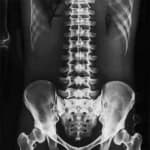

X Ray Scan in Dubai: Fast Bone & Chest Imaging

Digital technology for fractures, chest conditions, and joint assessment

X-ray remains the most widely used diagnostic imaging modality worldwide. In Dubai, it serves as the essential first-line investigation for a broad range of clinical concerns, from sports injuries and workplace accidents to chronic conditions like osteoarthritis and scoliosis. Our digital radiography system captures high-resolution images that allow radiologists to detect subtle findings that older film-based equipment might miss.

Scoliosis & Spinal Alignment

Full-spine X-ray is the standard imaging tool for measuring spinal curvature, monitoring progression in adolescents, and planning treatment strategies.